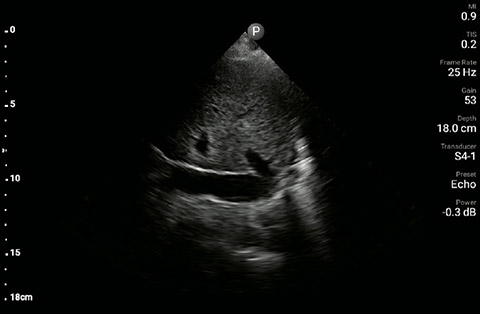

The patient had reduced LV systolic function without new or severe valvular pathology, a dilated, non-collapsing IVC, and diffuse B lines (left greater than right) on lung ultrasound imaging.

Parasternal long-axis

A 69 year-old male with a known history of hypertension, chronic non-oliguric kidney disease, insulin dependent diabetes, and chronic systolic heart failure with an ejection fraction (EF) of 25% secondary to ischemic cardiomyopathy was recovering in the CardioVascular ICU after four vessel coronary artery bypass grafting. His post-operative course had been complicated by acute respiratory failure, acute on chronic non-oliguric renal failure, delirium and pseudomonas pneumonia. The patient’s oxygenation had been improving on antibiotic therapy with aggressive diuresis and ionotropic support, although his BUN and creatinine remained quite elevated. Family had been reluctant to initiate dialysis given his clinical improvement and ability to make urine with diuretic support. The patient was extubated to high-flow oxygen by nasal cannula after successfully passing a spontaneous breathing trial, although, he had failed extubation one week prior secondary to acute dyspnea and hypoxia. Two days later, the patient began to have a fever, worsening shortness of breath with increased oxygen requirements, and inability to wean ionotropic and vasopressor support further. Because of concern for septic shock, the patient was given a total of 500ml of crystalloid overnight. Whole blood lactic acid levels returned at 1.6, serum creatinine increased from 5.8 to 6.11, and the patient’s fever and shortness of breath worsened. Repeat cultures were obtained and antibiotic therapy was broadened further while initiating non-invasive positive pressure ventilation for acute respiratory distress. In the interim, while awaiting laboratory results and chest X-ray imaging, POCUS with a three-point exam (F-TTE, IVC collapsibility, and lung ultrasound) was used for bedside evaluation of the etiology of the patient’s dyspnea. Within minutes, and with the additive information from the combined cardiac, subcostal IVC, and lung ultrasound imaging, the patient was diagnosed with acute on chronic congestive heart failure and flash pulmonary edema as the cause of his respiratory distress and hypoxia.